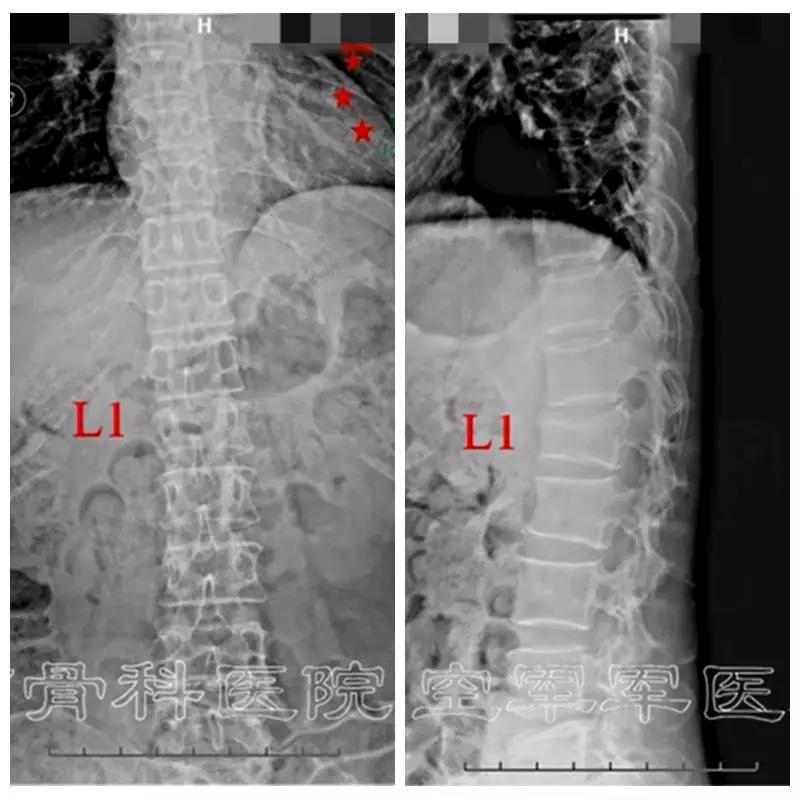

术前X线正侧位片

术前CT